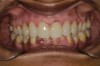

Fig 2. Preoperative frontal retracted 1:2 view.

Figure 2

A 40-year-old female patient complained of short teeth and asked for various options to improve her smile. On clinical examination, the palatal surfaces of the maxillary anterior teeth were found to be eroded, with the residual tooth structure having a smooth and shiny appearance (Figure 1 through Figure 3). In MIP, no restorative space was available, as the lower anterior teeth fit tightly into the upper palatal surfaces, making this a clinically challenging situation to treat conservatively. In most cases of conventional treatment protocols, such upper teeth are devitalized and restored with crowns that structurally leave the teeth in a compromised condition.10